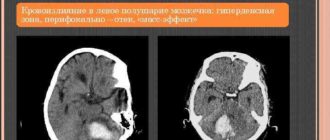

Микрокровоизлияния в левой гемисфере мозжечка

Инсульт мозжечка (мозжечковый инсульт): причины, симптомы, восстановление, прогноз © А. Олеся Валерьевна, к.м.н., практикующий